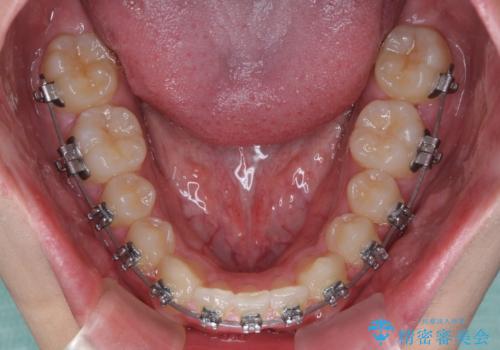

- メタルブラケット

- 1年1ヶ月

傾斜しいている大臼歯を立ち上げながら、下顎歯列を上顎に対して前方位となるように工夫し、デコボコを解消した上でディープバイトも改善することができました。